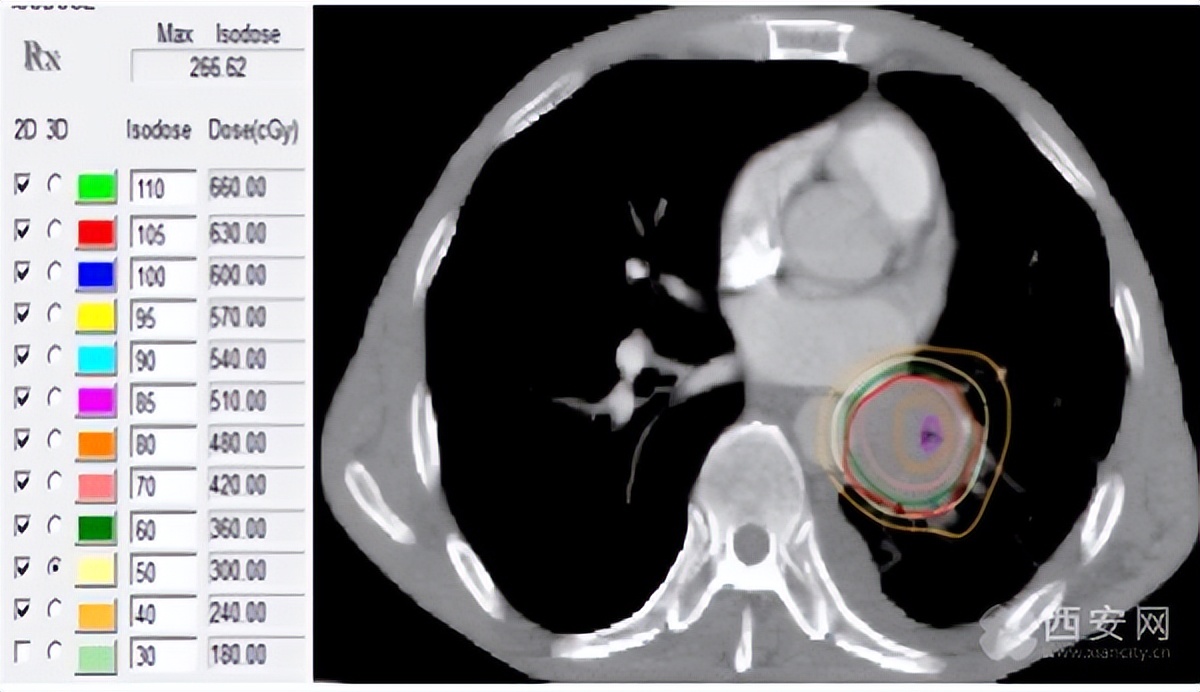

图1 调强适形放疗计划图显示右肺门病灶大小及放射治疗的范围和剂量分布。

图中提示左肺门鳞状细胞癌,治疗前病灶大小为4.1×3.8cm伴部分少量胸腔积液

在确保肺组织安全同时提高肿瘤中央区的剂量,达到局部根治的效果